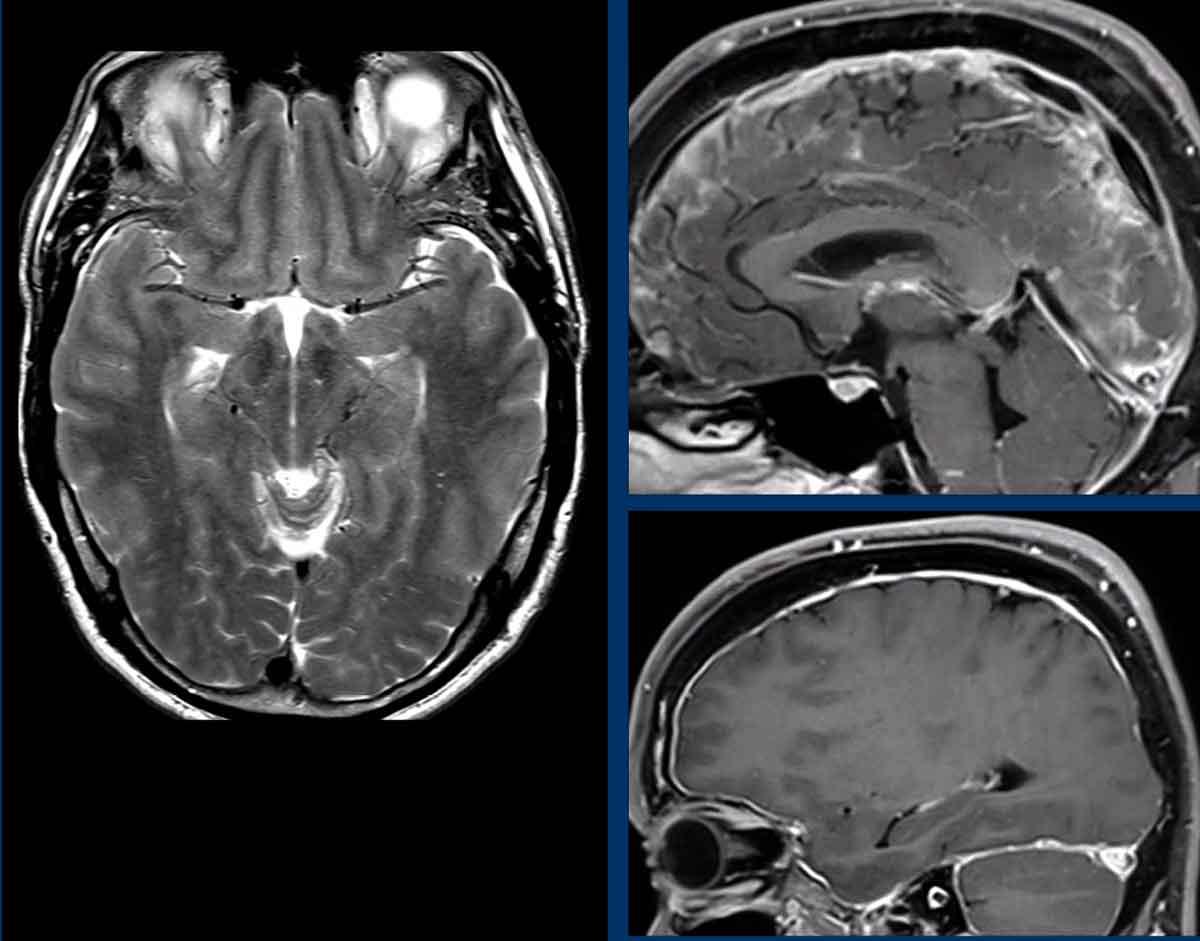

Hình ảnh

- Hình ảnh võng xuống với trung não bị chèn ép từ hai phía (vòng tròn).

- Trung não bình thường để so sánh.

Ở bệnh nhân SIH này, tất cả các tĩnh mạch đều giãn và bờ của xoang tĩnh mạch ngang có dạng lồi.

Lưu ý thêm hình ảnh màng cứng dày và ngấm thuốc.

Chuỗi xung FLAIR cho thấy các đặc điểm điển hình của hạ áp nội sọ tự phát:

- Giãn tĩnh mạch và xoang tĩnh mạch màng cứng

- Trung não bị võng xuống mức độ nhẹ

- Giảm khoảng cách thể vú – cầu não

- Tràn dịch dưới màng cứng hai bên trên chuỗi xung FLAIR axial (đầu mũi tên).

- Giãn tĩnh mạch và xoang tĩnh mạch màng cứng với bờ dưới lồi của xoang ngang (mũi tên đen).

- Trung não bị võng xuống và khoảng cách thể vú – cầu não giảm.

- Trung não bị võng xuống trên chuỗi xung T2W mặt cắt ngang.

- Ứ máu tĩnh mạch với bờ dưới lồi của xoang ngang.

- Màng cứng dày và ngấm thuốc.

- Giảm khoảng cách thể vú – cầu não.